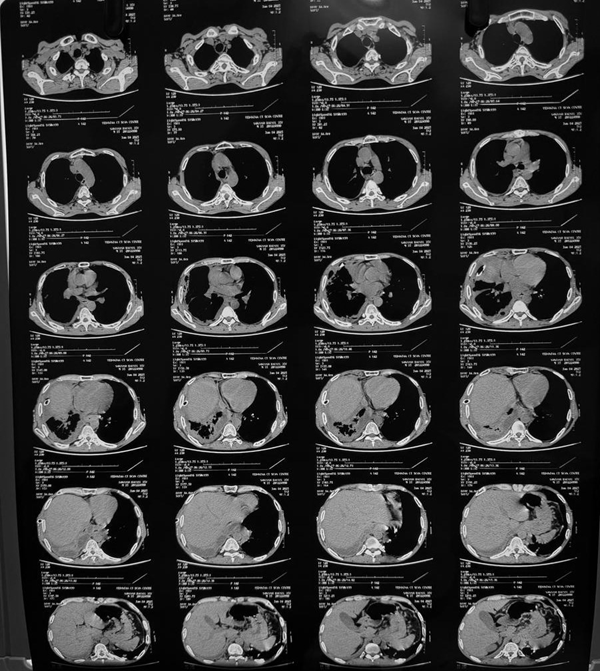

Postpartum Haemorrhage: A Case Series Highlighting Diverse Clinical Profiles and Evolving Management Strategies in a Tertiary Care Setting